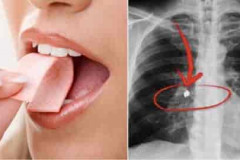

Արդյոք կարելի՞ է մաստակը կուլ տալ և արդյոք այն տարիներ շարունակ մնո՞ւմ է օրգանիզ...